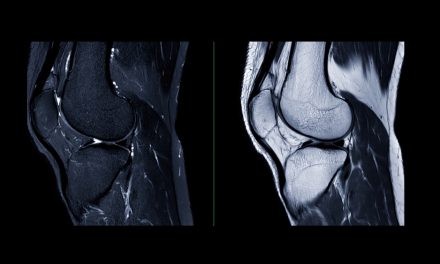

Because of its anti-inflammatory properties, MSM is commonly used for arthritis. Animal studies have shown reductions in cytokine production and, in some cases, lower CRP when MSM is used in combination with glucosamine [14-16]. Inflammatory cytokines such as TNF-α and IL-6 are implicated in cartilage destruction, and in vitro studies suggest MSM may help protect cartilage through this mechanism [7,17,18]. In animal models, MSM supplementation has reduced cartilage surface degeneration and improved joint findings [19,20].

Human studies have also been done. These studies are non-invasive and rely on questionnaires and joint function to measure results. Clinical trials suggest MSM may be effective in reducing pain, as indicated by the VAS pain scale and WOMAC pain subscale [21-24]. Improvements in physical function have also been reported [21-24].